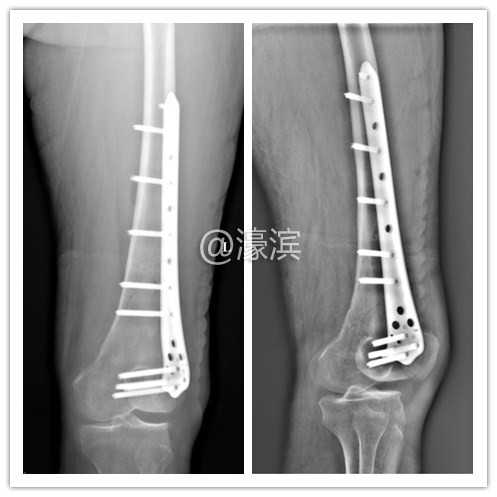

) }- R/ U9 Y  q) `+ i/ l+ f  我院专家团队会诊讨论,认为祁奶奶外伤后左大腿肿痛、活动障碍,有绝对手术指征,术前各项检查无明显手术禁忌症,可行骨折复位内固定术。切开复位、减少对骨折端血运干扰能够减少骨折不愈合发生机率。

▲手术后

在征得了祁奶奶及她的家人同意后,郭建陈主任于12月21日为祁奶奶行“左股骨远端骨折切开复位内固定术”,手术历时1小时50分钟。手术顺利结束后,患者转入ICU继续监护。病区护士密切观察患者生命体征及患肢末梢感觉及血运情况,在之后的几天中指导祁奶奶进行股四头肌及踝泵锻炼,以减少褥疮、深静脉血栓、肺部感染、尿路感染等机率。在医护人员的精心护理下,祁奶奶恢复得很快,她难以抑制心中的喜悦,托家人送来锦旗表示感谢。